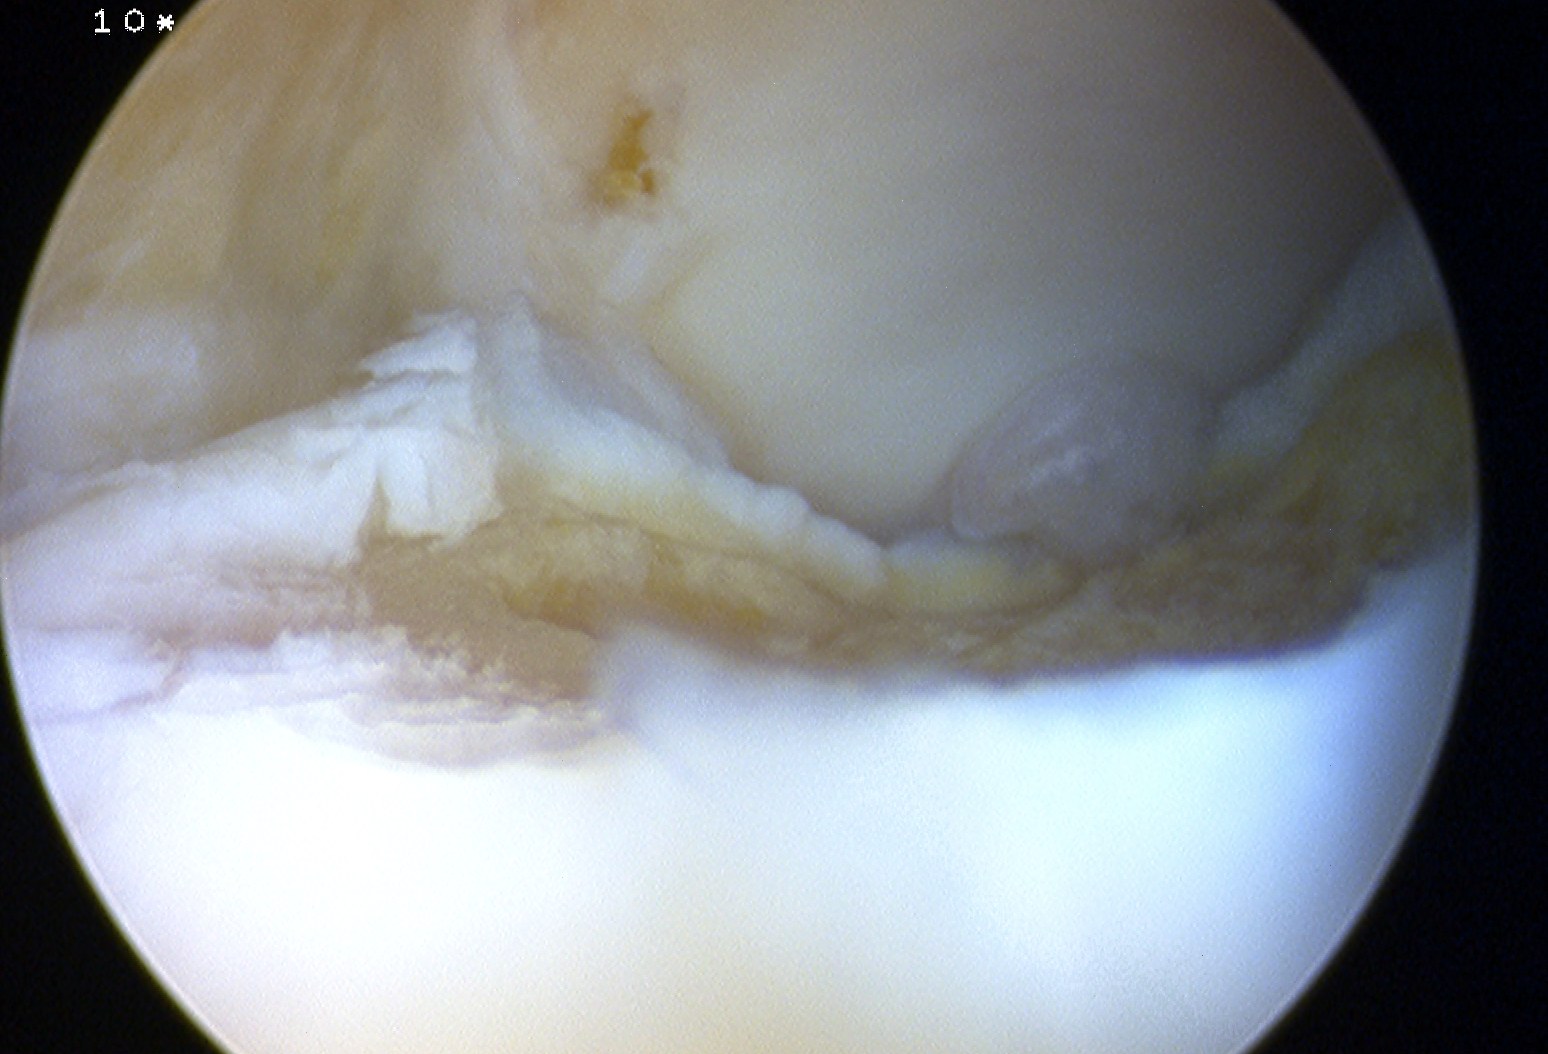

Arthroscopy techniques microfracture talus

Arthroscopy techniques AMIC talus

Arthroscopic techniques minced cartilage talus

Arthroscopic techniques osteochondral allograft